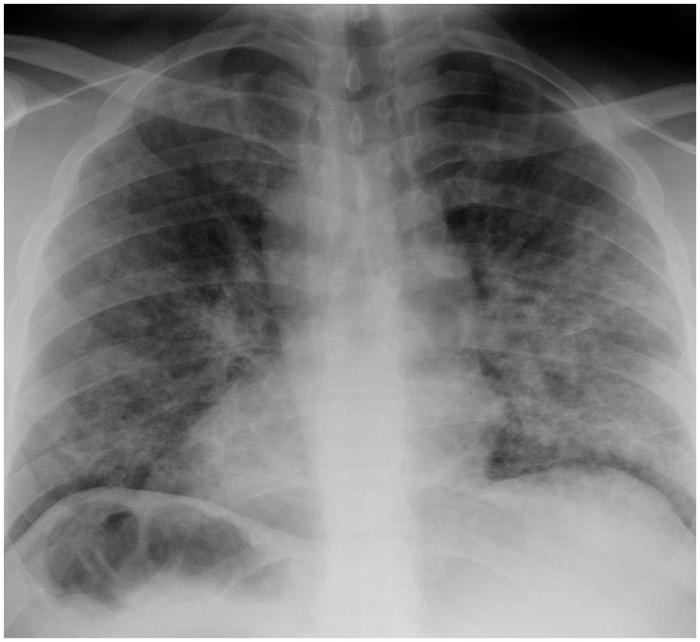

4. Рентгенографическое исследование позволит обнаружить изменения в легочной ткани.

image

2. При фибринозном плеврите пораженная сторона грудной клетки отстает при дыхании, выслушивается шум трения плевры, определяется укорочение перкуторного звука. При проведении рентгенографии легких обнаруживаются плевральные наслоения (шварты). По данным УЗИ плевральной полости экссудат не выявляется или определяется в скудном количестве.

3. Иная картина типична для экссудативного туберкулезного плеврита. Физикальное обследование выявляет сглаженность (при большом объеме экссудата – выбухание) межреберий, притупление перкуторного звука над областью скопления экссудата, смещение структур средостения в здоровую сторону. В острой фазе изменения гемограммы характеризуются значительным лейкоцитозом и ускорением СОЭ, лимфо- и эозинопенией. При рентгенологическом и ультразвуковом исследовании определяется свободная жидкость в полости плевры. Детальная оценка состояния легочной ткани возможна только после эвакуации экссудата. Диагноз гнойного плеврита подтверждается при получении гнойного экссудата во время плевральной пункции.